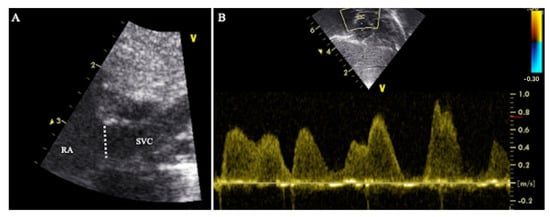

Figure 4. Axial or short axis view of the SVC. (A) The high frequency linear probe is placed near the left sternal edge (second intercostal space). (B) The ultrasound beam is perpendicular to SVC at the level of the right pulmonary artery. (C) The following structures are visualized: superior vena cava (SVC), aorta (Ao), right pulmonary artery (RPA).

Figure 5. Suprasternal view of the SVC. (A) The sector probe is placed near the suprasternal notch. The orientation marker is pointed towards 1:00 to 2:00. (B) The ultrasound beam is parallel to the SVC, (C) The following structures are visualized: superior vena cava (SVC), aorta (Ao), right pulmonary artery (RPA). The sample volume of the pulsed wave doppler (*) is placed in the SVC at the level of the RPA.